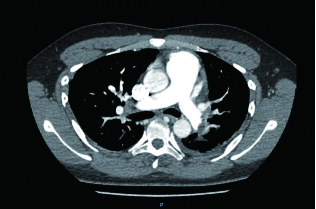

1 经典的挽救性溶栓治疗策略可能带给医生更多的是被动和难度例1 男性,28岁,体质量90 kg。主诉“胸闷、憋气1周加重1 d”。既往:体健;喜久坐(平均10~15 h/d);否认手术史、外伤史;入院查体:神志清楚,体温36.8℃,血压128/80 mmHg(1 mmHg=0.133 kPa),脉搏120次/min,呼吸26次/min,脉氧饱和度96%(安静,空气氧),未见明显乏氧征。双肺呼吸音清,未闻及干湿性啰音。心率120次/min,心律齐,P2 > A2,心界无扩大,无杂音。腹软,无压痛,肠鸣音正常,双下肢无浮肿。神经系统查体未见异常。血气分析(空气氧)提示pH 7.514,PaCO2 27.2 mmHg,PaO2 67.1 mmHg,SaO2 95.0%;D-Dimer:3 035 ng/mL,FDP 33.08 μg/mL,FBG 4.520 g/L;PLT 179.0 G/L,TNI 0.08 ng/mL,BNP 882.00 pg/mL;ALT 38 U/L,AST 17 U/L,CREA 82.6 μmol/L,血Na+、K+、Cl-正常范围;超声心动图(Ultrasonic Cardiogram,UCG)提示:右心增大,肺动脉主干及右肺动脉增宽,肺动脉主干32 mm,三尖瓣反流(重度),反流面积8.6 cm2,TI法估计SPAP为67 mmHg、左室舒末内径50 mm、左室E/A:45/38 cm/s, 左室壁厚度及运动正常,未见节段性室壁运动障碍;双下肢静脉超声提示左侧股静脉血栓形成可能(完全型)。心电图(图 1所示)提示窦性心动过速;肺动脉增强CT(Computed tomographic pulmonary angiography, CTPA)提示双肺主干明确充盈缺损(图 2所示)。入院诊断:急性肺血栓栓塞症(中高危)。入院后给予抗凝治疗(依诺肝素钠90 mg,皮下注射,1次/12 h)重叠华法令治疗的第4天D-Dimer升至47 482 ng/mL,第6天2 411 ng/mL。第7天常规复查双下肢超声未见新增血栓形成,复查UCG(当天INR 2.25)提示右心房漂浮血栓,并随心脏蠕动明显(图 3所示)。在准备胸外科手术取栓的过程中出现血压下降至70/40 mmHg,脉氧饱和度降至45%,立即给予气管插管并系统溶栓治疗(r-tPA 100 mg于2 h输注),溶栓治疗1.5 h患者血压逐渐回升并趋于稳定、溶栓治疗3 h自主呼吸开始恢复,于插管3天后(住院第10天)拔出气管插管,成功撤离呼吸机。溶栓过程中曾经出现消化道、气道出血,血红蛋白下降1.9 g/dL,未予输血治疗。溶栓后复查CTPA提示双肺主干血栓负荷明显减少,远段血液灌注明显增加(图 4所示)。

| 图 2 入院时CTPA提示双肺主干明确充盈缺损 |

| 图 4 溶栓后的CTPA肺动脉主干血栓负荷明显减少、远段血液灌注明显增加 |